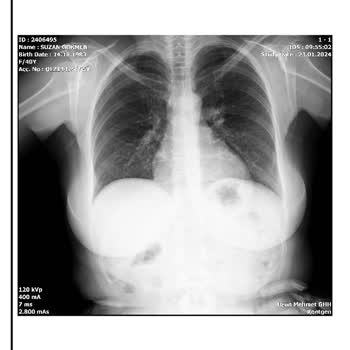

Yanlış teşhis koydu, egolu ve kaba tavrı kötüydü. Allah bir daha kimseyi onun eline düşürmesin. Başka bir hekime gösterdim, teşhisini ve adını sordu. 'Panik yapmayın' dedi ve kesinlikle başka bir doktora başvurun önerisinde bulundu. 'Sonuçlarınız kötü, ciğerleriniz bitik' dediği röntgen filmi için h...